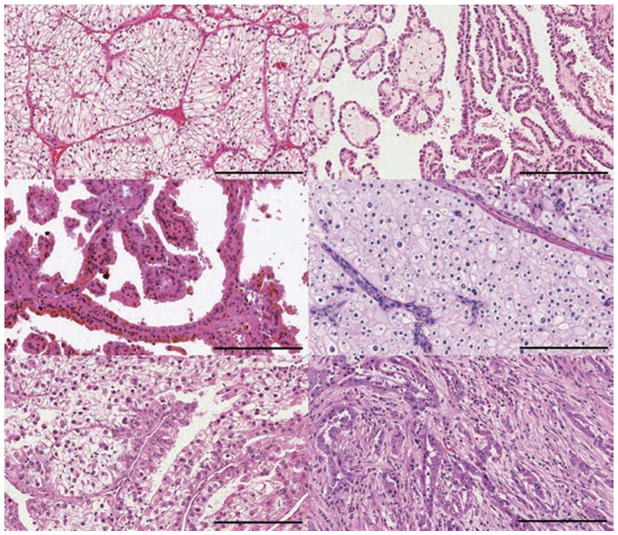

肾细胞癌 (RCC) 包括一组源自肾小管上皮细胞的异质性癌症,是全球 10 种最常见的癌症之一。 在过去二十年中,肾细胞癌 (RCC)的组织病理学和分子表征方面的重要进展导致对其分类进行了重大修订。 发病率≥5% 的主要亚型是透明细胞肾细胞癌 RCC (ccRCC)、乳头状肾细胞癌 RCC (pRCC)和嫌色细胞肾细胞癌 RCC (chRCC)(图 1)。 其余亚型非常罕见(每种亚型的总发病率≤1%),如果肿瘤不符合任何亚型诊断标准,则将其归为未分类 RCC(uRCC,总发病率约为 4%)。 透明细胞肾细胞癌是最常见的亚型,占肾癌死亡的大部分,是佳学基因肾细胞癌基因检测的重点。 事实上,由于透明细胞组织学在转移性疾病中占主导地位 (83-88%),具有非透明细胞组织学的肿瘤已被归类为“nccRCC”(表 1),以便进行临床试验的可行性。 此外,最近的癌症基因组研究揭示了 ccRCC 肿瘤内和肿瘤间异质性的明显复杂性,这可能导致观察到的异质性临床结果。